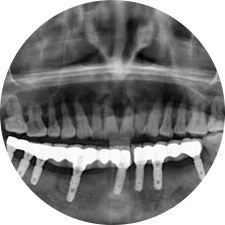

口腔種植是將人工牙根通過(guò)手術(shù)植入牙骨內(nèi),獲得牙槽骨牢固的支持,通過(guò)特殊的裝置和方式連接牙修復(fù)體,獲得與天然牙功能、結(jié)構(gòu)以及美觀相似的效果。

河北惟德口腔醫(yī)院擁有國(guó)內(nèi)豐富的半口/全口、即刻負(fù)重種植案例,十八年案例跟蹤分析,總結(jié)梳理出的各種不同類(lèi)型的種植案例,Nobel種植體系針對(duì)半口/全口缺牙患者,通過(guò)4-8顆種植體可快速達(dá)到牙齒重建,不僅植入種植體較少,節(jié)省費(fèi)用,手術(shù)時(shí)間更短。

術(shù)前患者CBCT口掃1:1三維重建,模擬手術(shù)過(guò)程及預(yù)測(cè)術(shù)后治療效果,確定每顆植體植入的適合的種植位點(diǎn)、深度及角度,有效避免損傷頜骨重要解剖結(jié)構(gòu),提高手術(shù)準(zhǔn)確度與安全性。

惟德口腔種植體系是以患者感受為中心,取代傳統(tǒng)種植牙手術(shù)需要翻瓣、打孔、縫合,術(shù)前、術(shù)中、術(shù)后的繁復(fù)流程,采用3D導(dǎo)航微創(chuàng)準(zhǔn)確種植技術(shù),通過(guò)數(shù)字化CAD/CAM掃描技術(shù)獲得缺牙患者口腔數(shù)據(jù),以數(shù)據(jù)為基礎(chǔ)重建口腔模型進(jìn)行模擬種植。

術(shù)前將患者口內(nèi)的CBCT數(shù)據(jù)及咬合關(guān)系上傳到計(jì)算機(jī)中,建立1:1三維重建,模擬手術(shù)過(guò)程及預(yù)測(cè)術(shù)后治療效果,找出較佳種植位點(diǎn)、深度及角度,獲取實(shí)際種植體在頜骨內(nèi)的具體三維位置,有效避免損傷頜骨重要解剖結(jié)構(gòu),大大降低手術(shù)風(fēng)險(xiǎn),提升種植成功率。